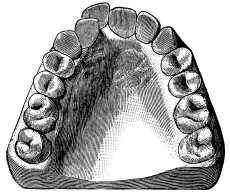

A correct acquaintance with the disposition of the alveoli of the teeth is of importance for skilful and successful operating. Fig. 15 gives a general idea of the appearance of the alveoli, but it is needless to say that a full knowledge can only be really obtained by a careful study of the bones themselves; by this means, too, some idea of the strength of different portions of the alveolar borders can be obtained—a matter of some moment when applying force in the process of removing a tooth from its socket. The points to be specially noted in the maxilla are the thinness of the outer alveolar wall as compared with the inner, the prominence of the canine socket, and the cancellous character of the bone in the region of the third molar. In the mandible the outer alveolar border will be seen to be thinner than the inner, with the exception of that portion in the region of the{13}